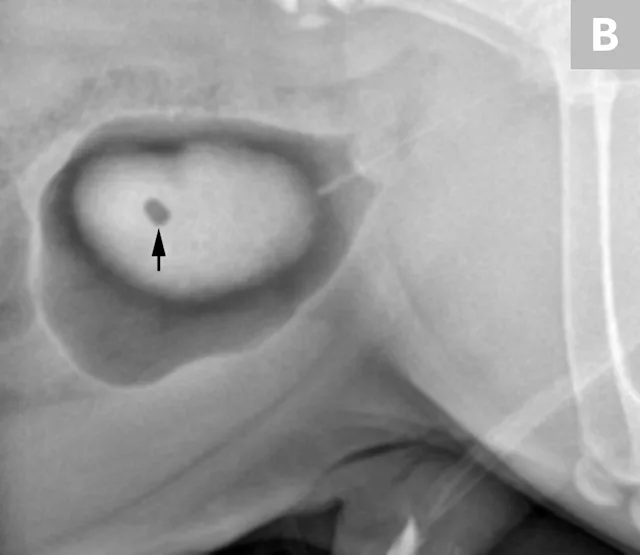

FIGURE 9A

1 / 2

Lateral radiograph of a bulldog presented for recurrent hematuria and stranguria. The study was negative for mineral opaque urinary bladder calculi.